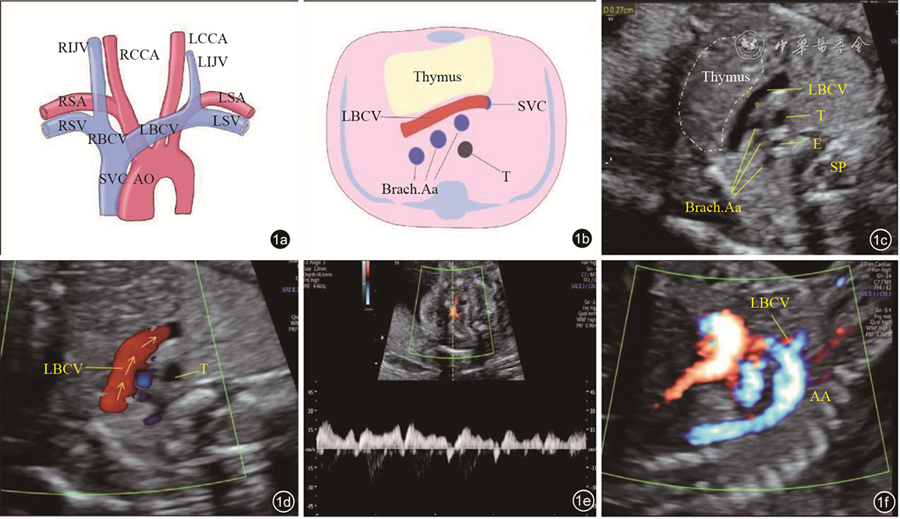

The 43 cases of LBCV abnormalities included the following three types: Abnormal course of the LBCV (traveling under the aortic arch in 25 fetuses, penetrating the thymus in 6, and retroesophageal or retrotracheal LBCV in 2); absent LBCV in 7 fetuses; and abnormal diameter of the LBCV (significantly widened inner diameter in 2 fetuses, and smaller inner diameter in 1). Nineteen were detected with other malformations, including right aortic arch, tetralogy of Fallot, transposition of the great arteries, persistent left superior vena cava, and total anomalous pulmonary vein communication. The mean inner diameter of the LBCV in normal fetuses at 18 to 34 weeks ranged from 1.9 mm to 3.98 mm, which showed a positive linear correlation with gestational age. The regression equation was: LBCV inner diameter (mm)=-0.6796+0.1352× gestational age (GA).

The position, course, and morphology of the LBCV can be observed by prenatal ultrasound. The inner diameter of the normal LBCV increases linearly with gestational age. Knowing the ultrasonographic features and clinical significance of different types of LBCV abnormalities can provide information and evidence for clinical consultation.